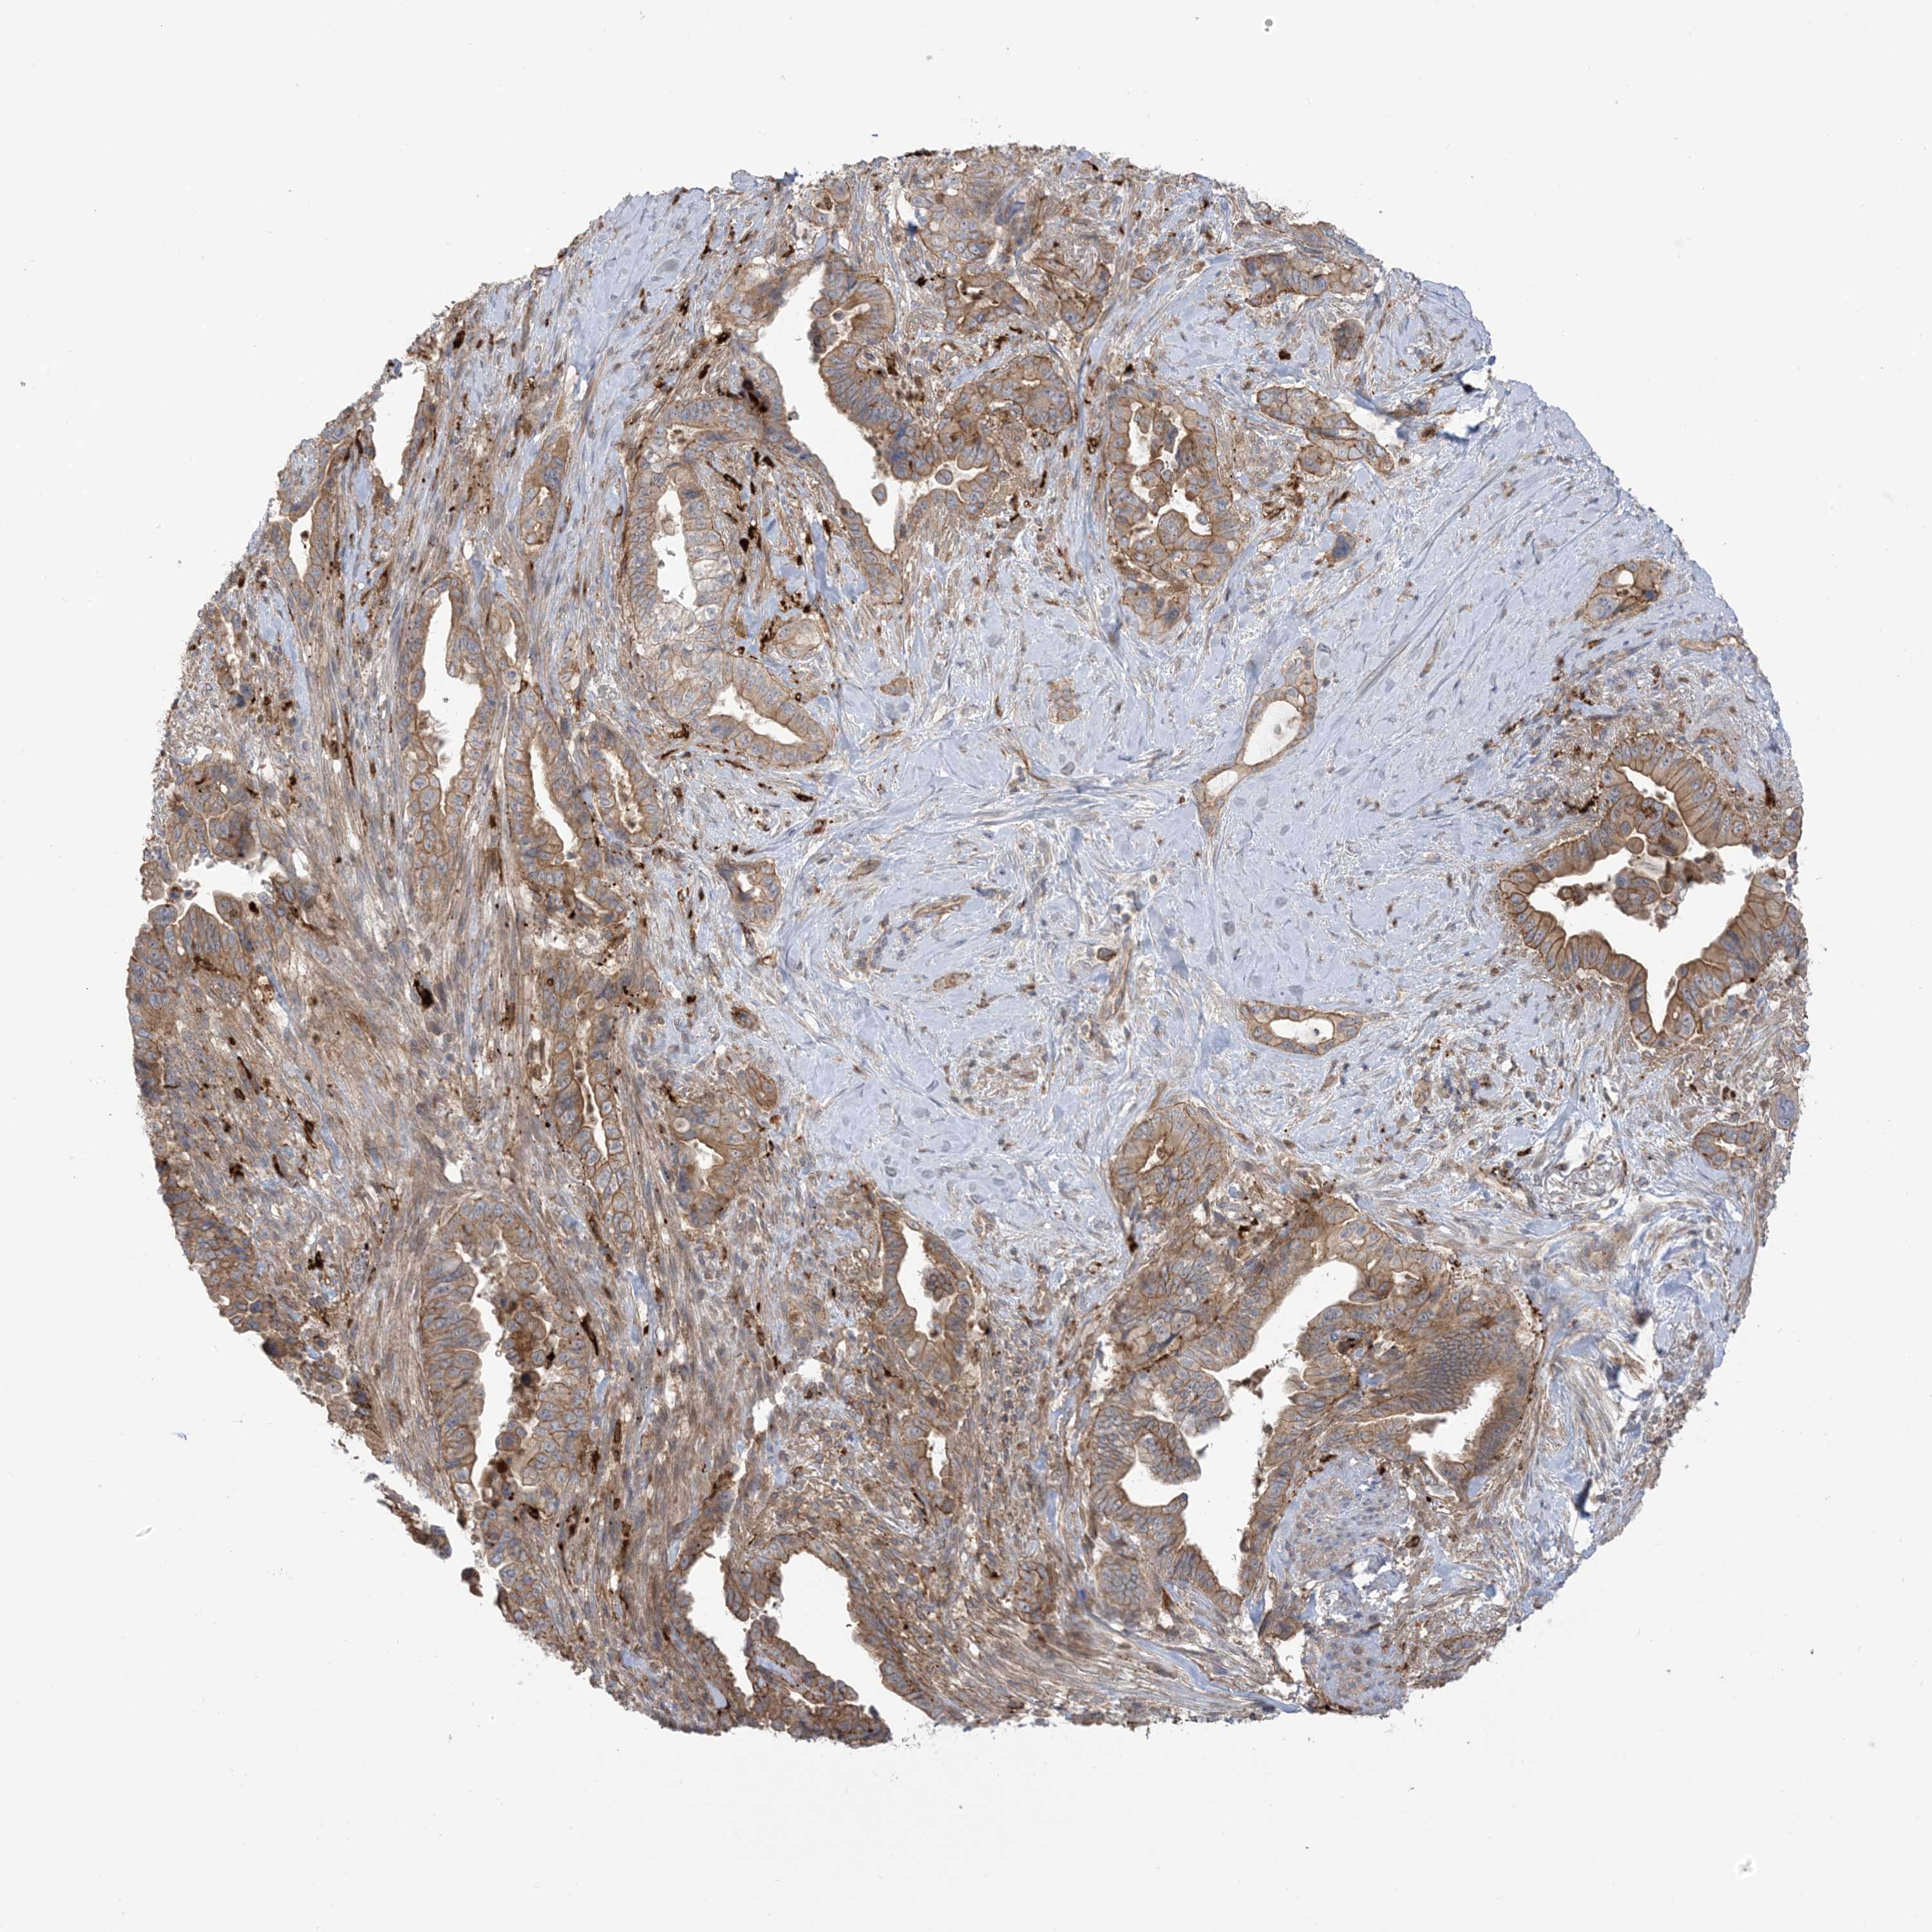

PANCREATIC CANCER - Protein expressioni

A mouse-over function shows sample information and annotation data. Click on an image to view it in a full screen mode. Samples can be filtered based on level of antibody staining by selecting one or several of the following categories: high, medium, low and not detected. The assay and annotation is described here.

Note that samples used for immunohistochemistry by the Human Protein Atlas do not correspond to samples in the TCGA dataset.

Antibody stainingi

Antibody staining in the annotated cell types in the current human tissue is reported as not detected, low, medium, or high, based on conventional immunohistochemistry profiling in selected tissues. This score is based on the combination of the staining intensity and fraction of stained cells.

Each image is clickable and will lead to virtual microscopy that enables deeper exploration of all samples and also displays staining intensity scores, fraction scores and subcellular localization as well as patient and tissue information for each sample.

Antibody HPA032024

Antibody HPA032025

Adenocarcinoma, NOS